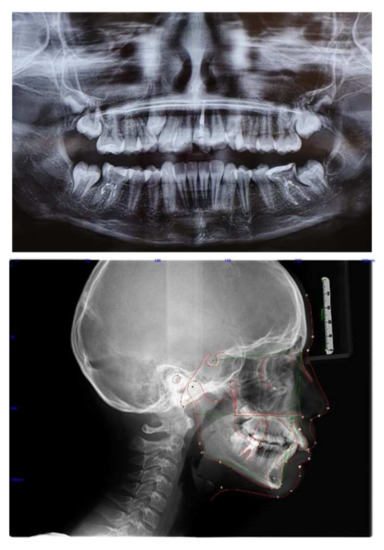

Figure 5.

Radiograph post Herbst and cephalometric analysis.

To achieve the treatment objectives, a hybrid palatal expander was initially applied, anchored to two palatal miniscrews and to first upper molars bands, to prepare the arch in a transverse direction. The patient’s parents gave their informed consent for the treatment. Having obtained an adequate size of the upper arch in a sagittal and transverse direction, the Herbst appliance was applied and anchored superiorly to the hybrid palatal expander to allow mandibular advancement and at the same time avoid excessive retroclination of the upper incisors and distalization of the upper molars, which could lead to an excessive increase in the nasolabial angle during Herbst therapy (Figure 4 and Figure 5).

After seeing the obtained results, we would again select the same treatment plan today (Figure 5, Figure 6, Figure 7, Figure 8 and Figure 9).

Post-treatment radiographs and cephalometric analysis.